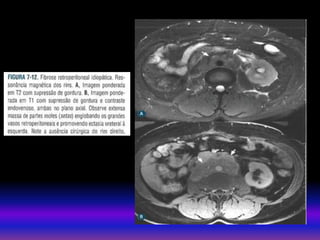

• RNM Secuencias convencionaisT1 e T2 permitem a detecção de anormalidades estruturais e vasculares. Util a RNM com gadolínio para pacientes alergicos aos contrastes iodados. Há risco de fibrose nefrogênica sistemica pelo gadolínio (regras): Ter creatinina dos pacientes maiores de 60 anos. TFG entre 60 – 30 ml risco/benefício TFG menor 30 ml Não usar. MÉTODOS DE IMAGEM